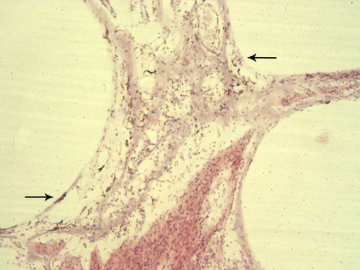

Immunohistochemical study of the cause of sensorineural hearing loss due to cochlear otosclerosis. In 1969 this laboratory reported, in the face of much controversy, for the first time a relationship of sensorineural hearing loss and the amount of otosclerosis involving the cochlear capsule. The reason for the hearing loss has yet to be determined. However in severe cases of hearing loss there are changes in the spiral ligament (hyalinization signifying aseptic cellular death) seen in no other pathological conditions affecting the inner ear. We hypothesize that the same enzymes, that are responsible for the normal bone dissolution that occurs as the otospongiosis advances through the cochlear capsule, diffuse into the spiral ligament result in cell death and replacement with hyaline and a toxic suppression of the function of the organ of Corti. We are currently investigating (using immunohistochemistry (Fig 4)) various enzymes that might be responsible for the hyalinization and cochlear malfunction.

Immunohistochemistry is a method of identifying specific proteins within a cell or area. An antibody is linked to a specific chromogen or fluorescent dye and examined through a light, ultra-violet, or confocal microscope (Figs 7a and 7b) (Arnold W, Acta Otol, 1987, 436(supp):62-8.